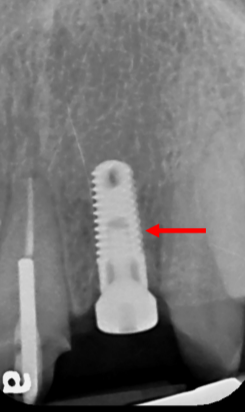

Precision Implant Placement always begins with meticulous planning using CBCT scans and dedicated implant‐planning software (Figs. 1-3). First, we virtually “insert” the implant on the CT scan so it centers beneath the future crown (Fig. 1). Then we design and fabricate a surgical guide (Fig. 2) to transfer that plan directly to the patient’s mouth. Finally, the guide seats on the patient’s teeth during surgery to ensure exact implant placement (Fig. 3), achieving both optimal bone support and prosthetic alignment.

Fig. 3: Surgical Guide Seated on the Teeth to Guide Implant Drills